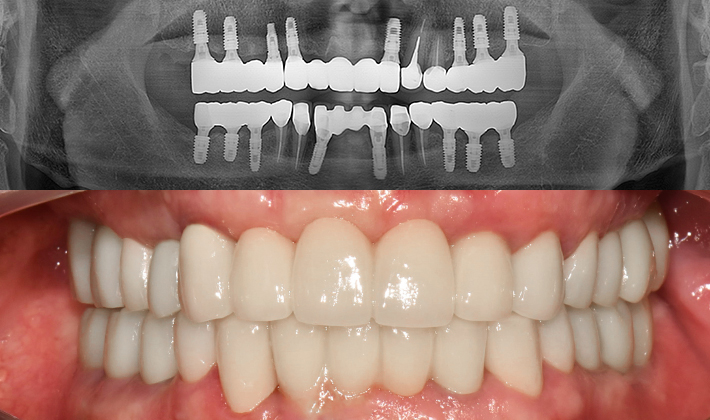

치과가 무서워 10년 동안 미뤄온 임플란트 수술 그 결과는?

2026.01.21